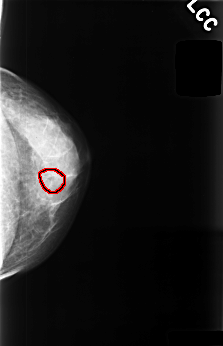

C_0477_1.LEFT_MLO

C_0477_1.LEFT_CC

LEFT_CC LINES 4488 PIXELS_PER_LINE 2896 BITS_PER_PIXEL 12 RESOLUTION 50 OVERLAY

FILE: C_0477_1.LEFT_CC.OVERLAY

TOTAL_ABNORMALITIES 1

ABNORMALITY 1

LESION_TYPE CALCIFICATION TYPE PUNCTATE DISTRIBUTION CLUSTERED

ASSESSMENT 4

SUBTLETY 3

PATHOLOGY BENIGN

TOTAL_OUTLINES 1

BOUNDARY